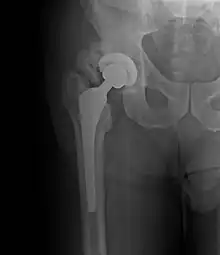

A ossificação heterotópica é comum após trauma físico grave, especialmente quando envolve lesão medular, e em vários tipos de cirurgia ortopédicas. Alguns casos só são perceptíveis com um exame de raio X enquanto os mais graves podem causar deformações sérias, dor e incapacitar certos movimentos.[3]

O tratamento geralmente envolve cirurgia para reposicionar o(s) órgão(s) ou osso(s) afetado(s), utilização prótese e longos períodos de fisioterapia. Alguns medicamentos típicos de pós-cirúrgicos como antibióticos e anti-inflamatórios podem ser usados para evitar complicações e analgésico pode ser prescrito para diminuir a dor.